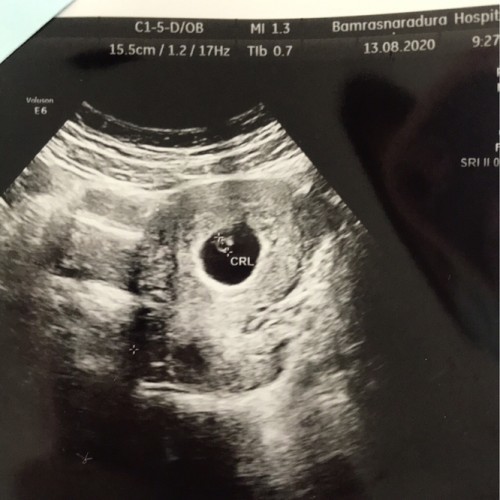

ตั้งท้องได้6สัปดาห์อัลตร้าซาวด์วันนี้หมอบอกว่าเห็นแต่ถุงตั้งครรภ์ยังไม่เห็นน้องค่ะ นัดอัลตร้าซาวด์ใหม่เดือนหน้า

ของเรา 6W4D ซาวเมื่อวาน(13/8/63) จิ้มปุ๊บเจอเลย ตัวกะติ้ด ยาว 0.62cm.